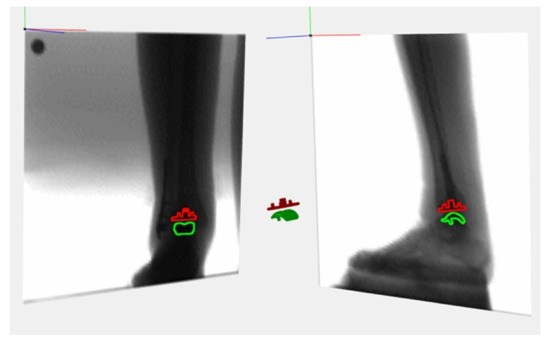

- Bonanzinga, T.; Signorelli, C.; Bontempi, M.; Russo, A.; Zaffagnini, S.; Marcacci, M.; Bragonzoni, L. Evaluation of RSA set-up from a clinical biplane fluoroscopy system for 3D joint kinematic analysis. Joints 2016, 4, 121–125. [Google Scholar] [CrossRef]